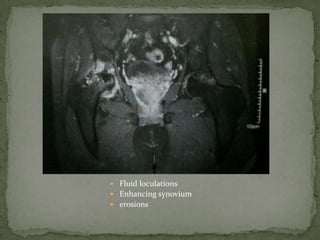

 Fluid loculations

 Enhancing synovium

 erosions